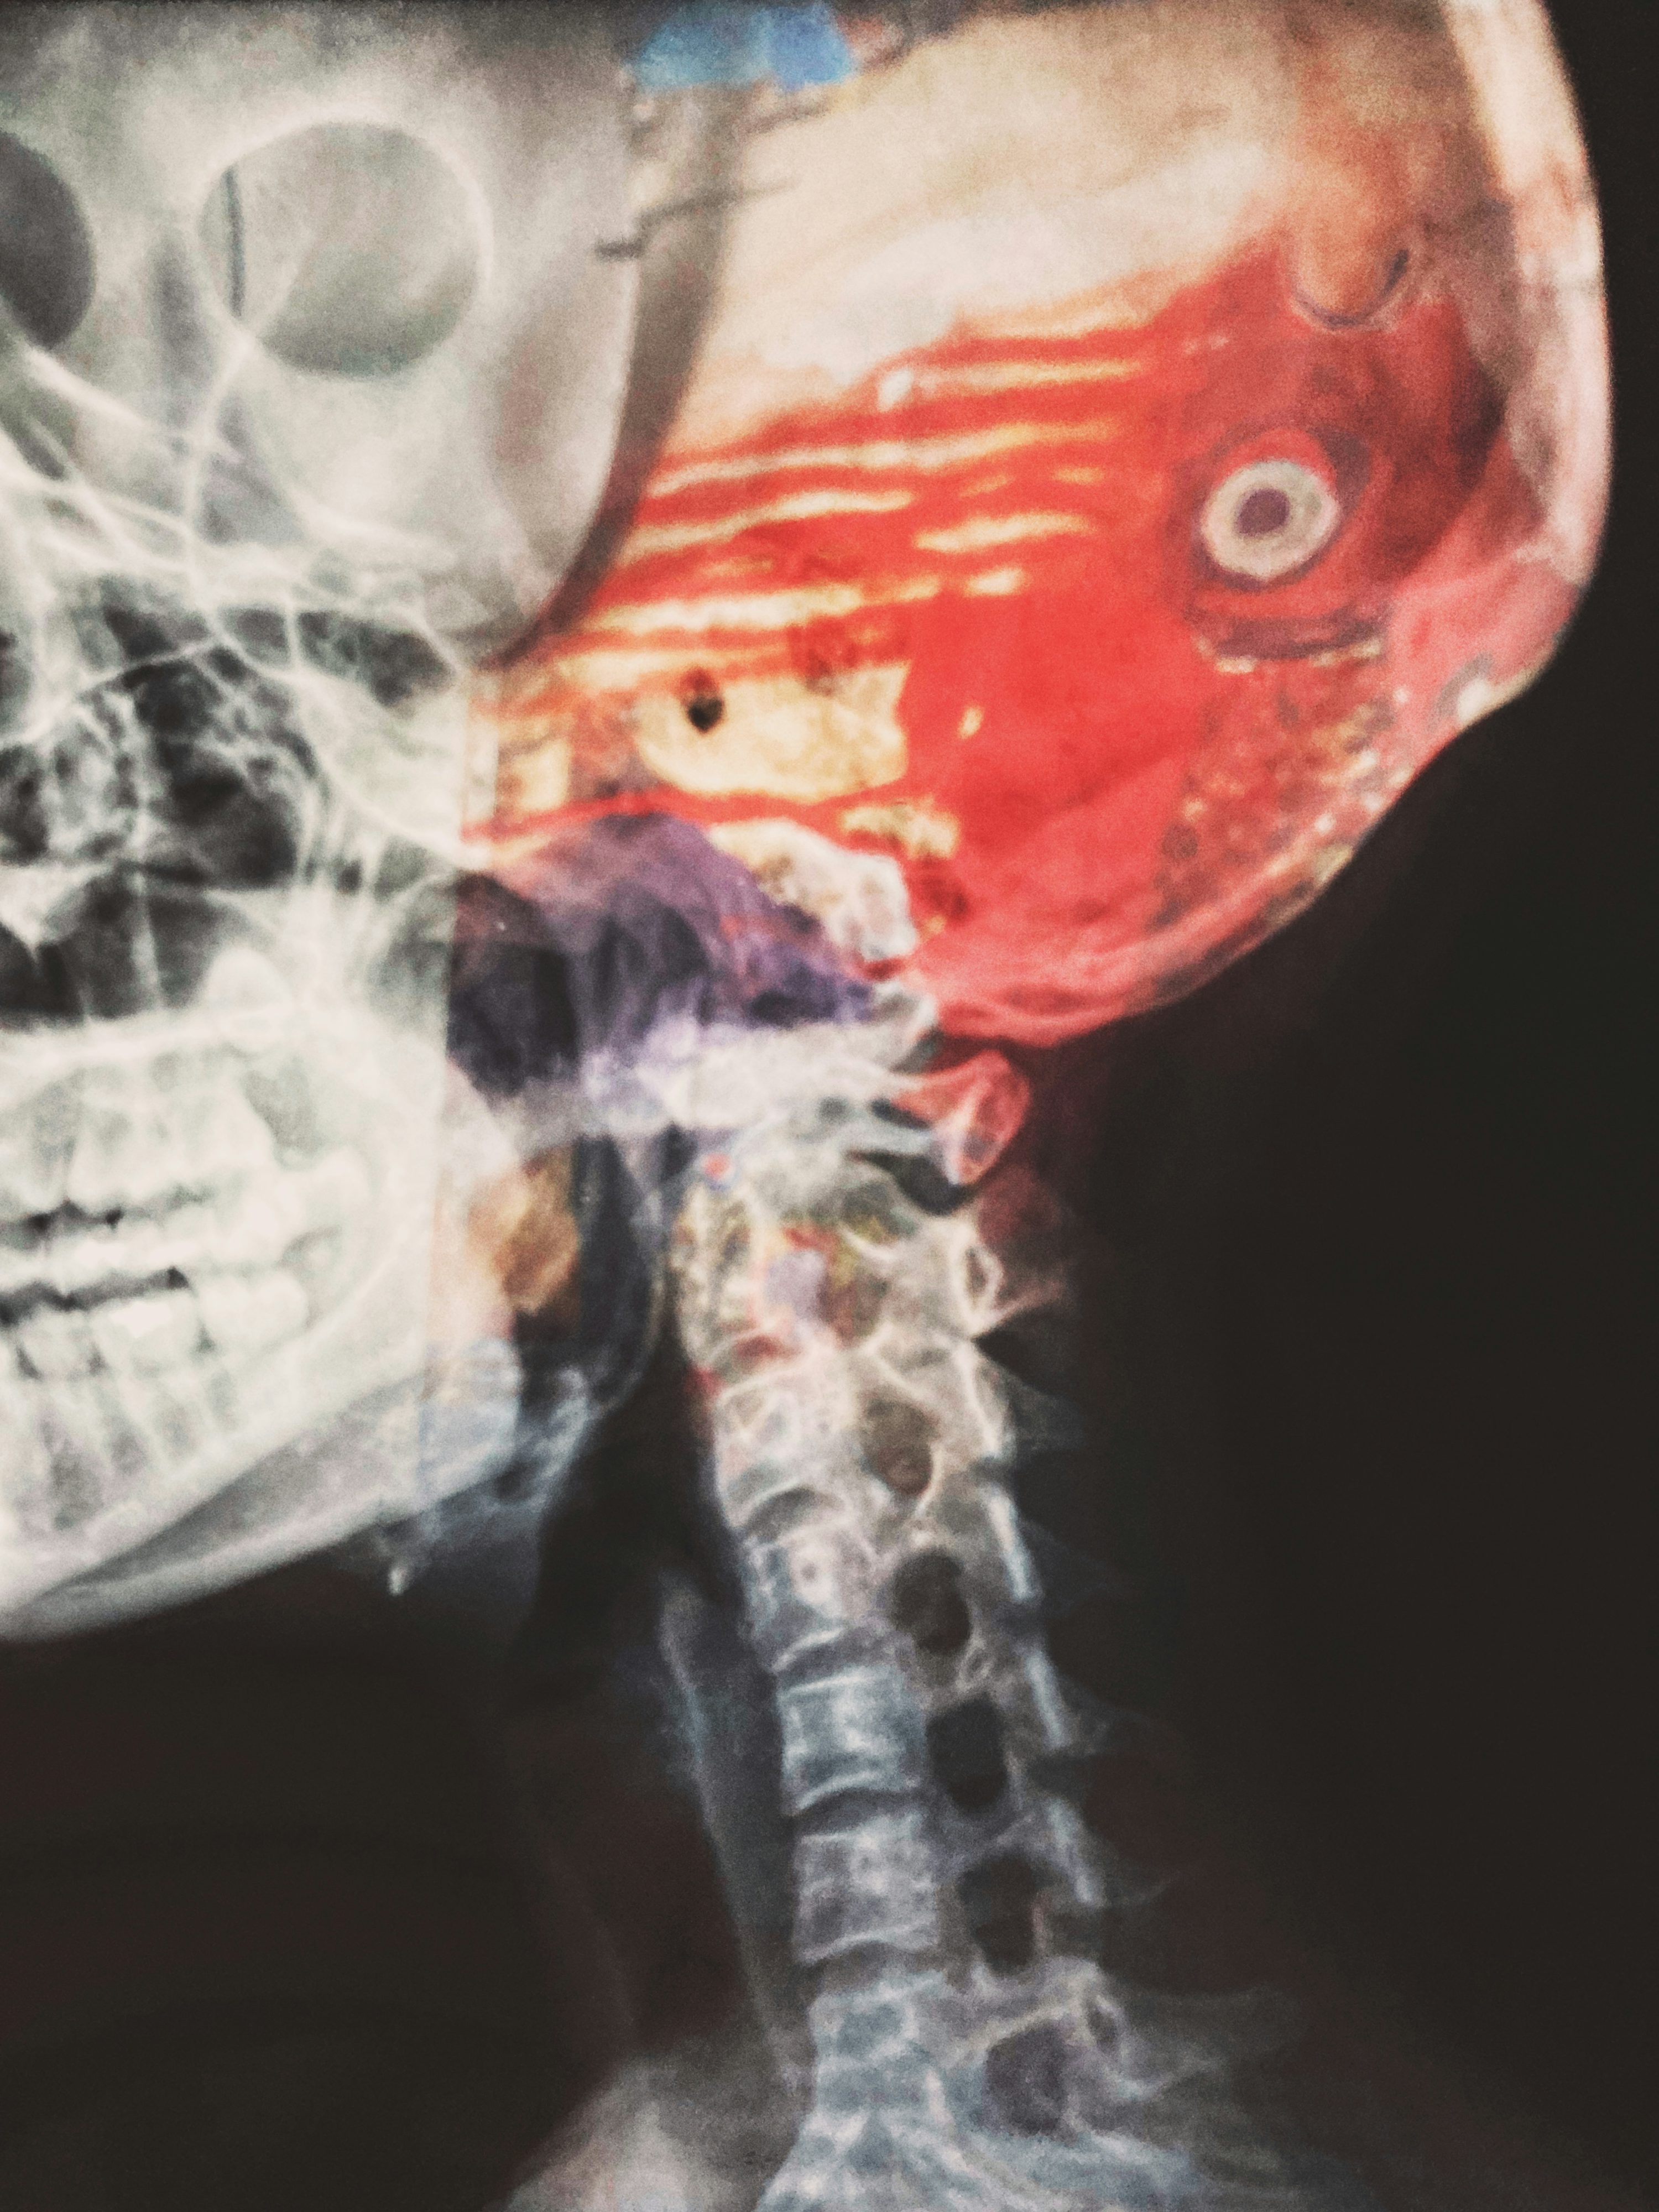

하지만 모든 환자가 혈전용해술을 받을 수 있는 것은 아닙니다. 최근 수술을 받았거나 출혈 위험이 높은 경우, 혈압이 매우 높은 경우, 임신 중인 경우 등은 금기 사항에 해당합니다. 또한 CT 촬영에서 출혈이 확인되거나 뇌경색 범위가 너무 넓은 경우에도 시행하지 않습니다. 의료진은 신속하게 환자 상태를 평가하여 치료 가능 여부를 판단합니다.

혈전용해술의 가장 큰 부작용은 뇌출혈입니다. 약 6%의 환자에서 증상성 뇌출혈이 발생할 수 있으며, 이는 치명적일 수 있습니다. 따라서 치료 후 24시간 동안 중환자실에서 집중 관찰하며, 신경학적 상태와 혈압을 면밀히 모니터링합니다. 혈압이 상승하지 않도록 조절하고, 항혈전제나 항응고제는 24시간 동안 투여하지 않습니다. 치료의 위험성에도 불구하고 이득이 훨씬 크므로 골든타임을 놓치지 않는 것이 중요합니다.